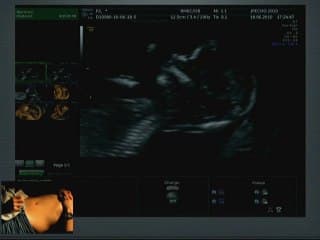

La plus grande ressource vidéo en échographie fœtale de France. Conférences, cours magistraux, démonstrations pratiques et podcasts par les experts du Collège Français d'Échographie Fœtale.

La médiathèque du Collège Français d'Échographie Fœtale (CFEF) constitue l'une des plus importantes collections de ressources vidéo dédiées à l'échographie fœtale en France. Avec plus de 3 261 vidéos, elle couvre l'ensemble des thématiques liées à la pratique échographique prénatale.

Vous y trouverez des conférences présentées lors des congrès nationaux et internationaux, des cours magistraux dispensés par des experts reconnus, des démonstrations pratiques sur des cas cliniques réels, ainsi que des podcasts et tables rondes sur les dernières avancées de la spécialité.